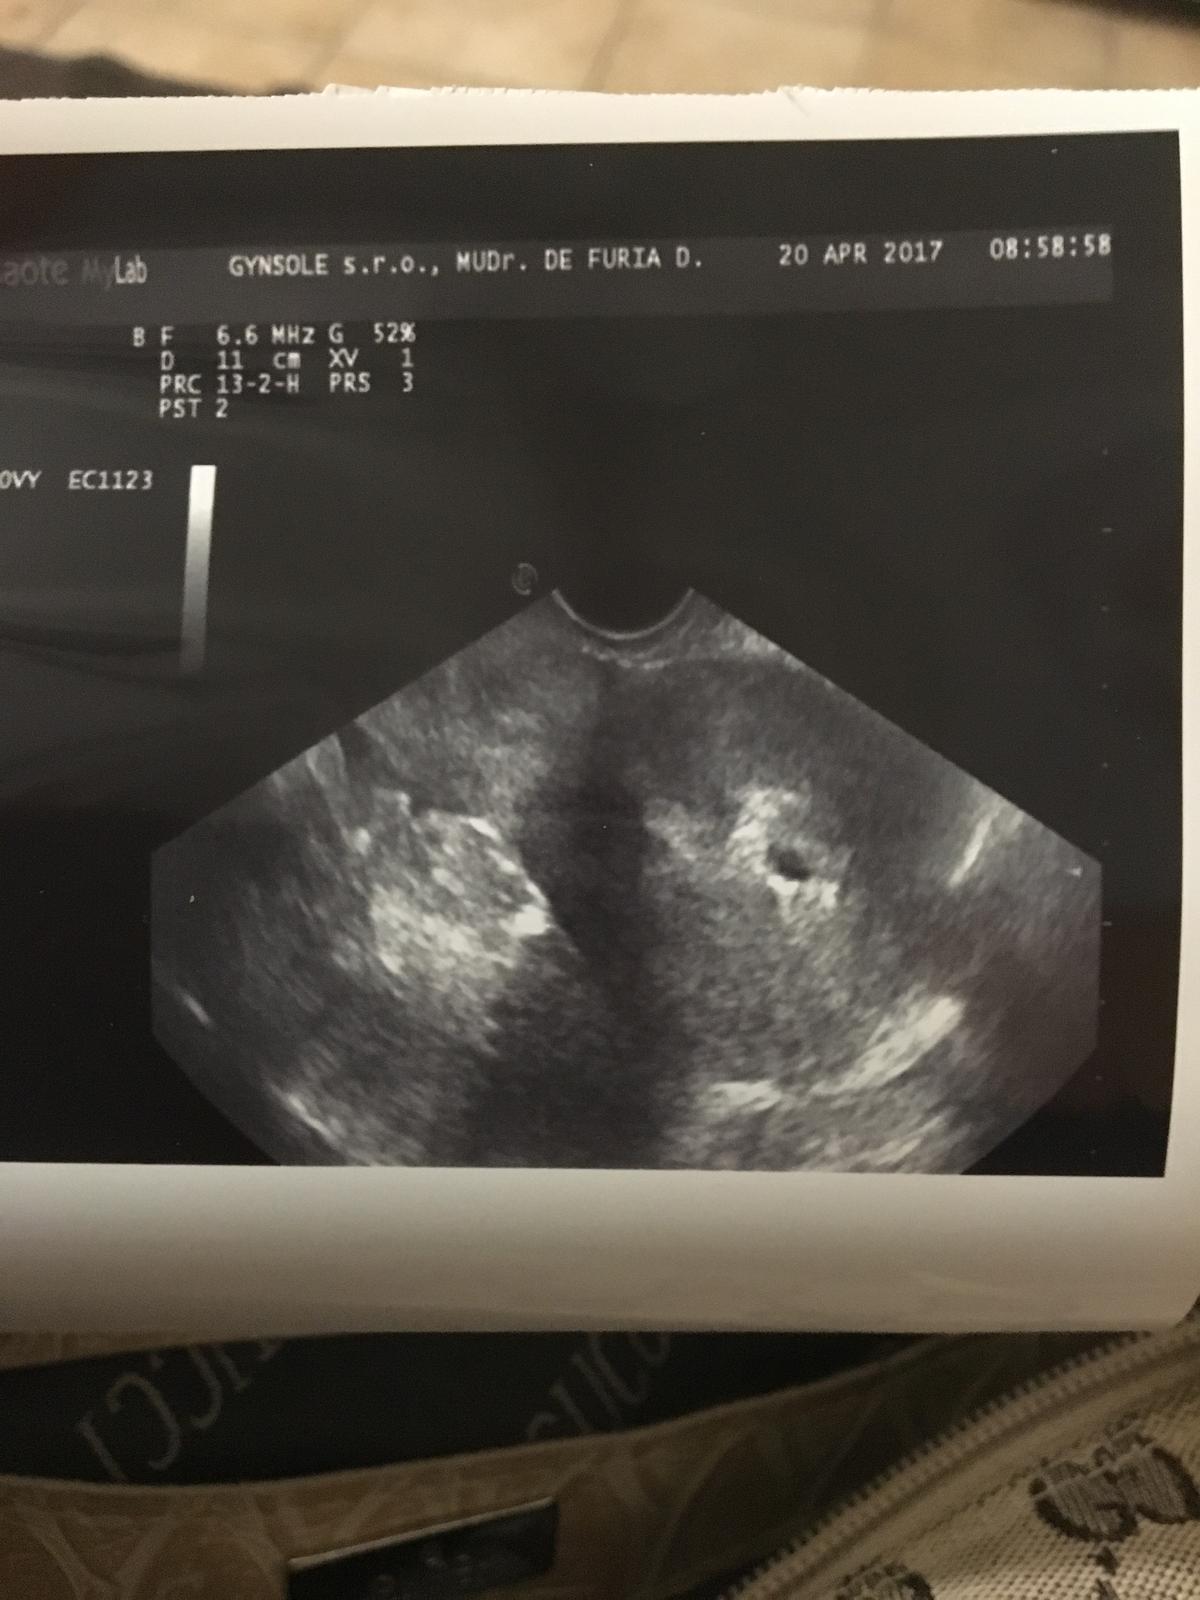

@bluebell0412 @miriamn76 @luta13 @happymia a všetky ostatne babulky a tehulky som šťastná žena fakt až mám szly šťastia tu je moja fazuľka hneď sa ukázala ešte je malinká ale verím že bude pekne rast 😍😍